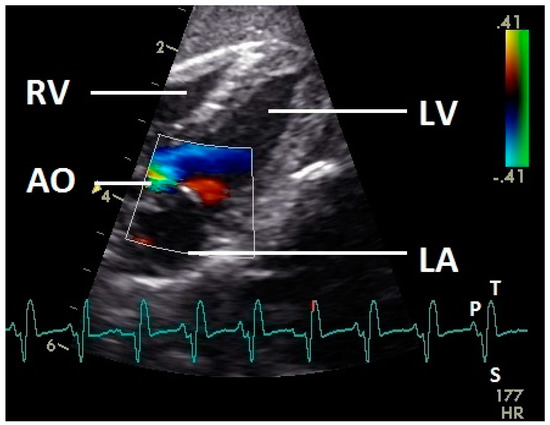

Left ventricular ejection, displayed as a blue flow signal, was observed during systole (ascending part of S wave to descending part of T wave of ECG) in the ventricle, left ventricular outflow tract, and aorta. This blue flow signal was aliased in all pigeons especially in the aorta with our settings. In the first part of the systole in all pigeons a simultaneous red ventricular blood flow signal to the much larger blue signal under the AV (Figure 4) valve was observed. During the closure of the aortic valve a little red signal in the area of this heart valve was realized in some pigeons (n = 11).

Figure 4.

Color Doppler image of the left ventricle in the systole. The blood ejection from the left ventricle in the aorta is visible (blue signal). The blue flow signal is aliased in the aorta (wrong direction: red instead of blue of the color Doppler signal in the aorta). The movement of the valve level of the heart and the resulting blood flow are visible as a red signal. LV: left ventricle; LA: left atrium; AO: aorta; RV: right ventricle; HR: heart rate. Electrocardiogram: P: P wave, S: S wave, T: T wave. The color scale on the right of the image is calibrated in m s−1.

In the preejection period, between the end of the active diastolic filling and the contraction of the ventricle myocardium, we found in two pigeons (4.7%) a blue blood flow signal between the leaflets of the left AV valve to the atrium, a sign of an insufficiency of the left AV valve in this heart phase.